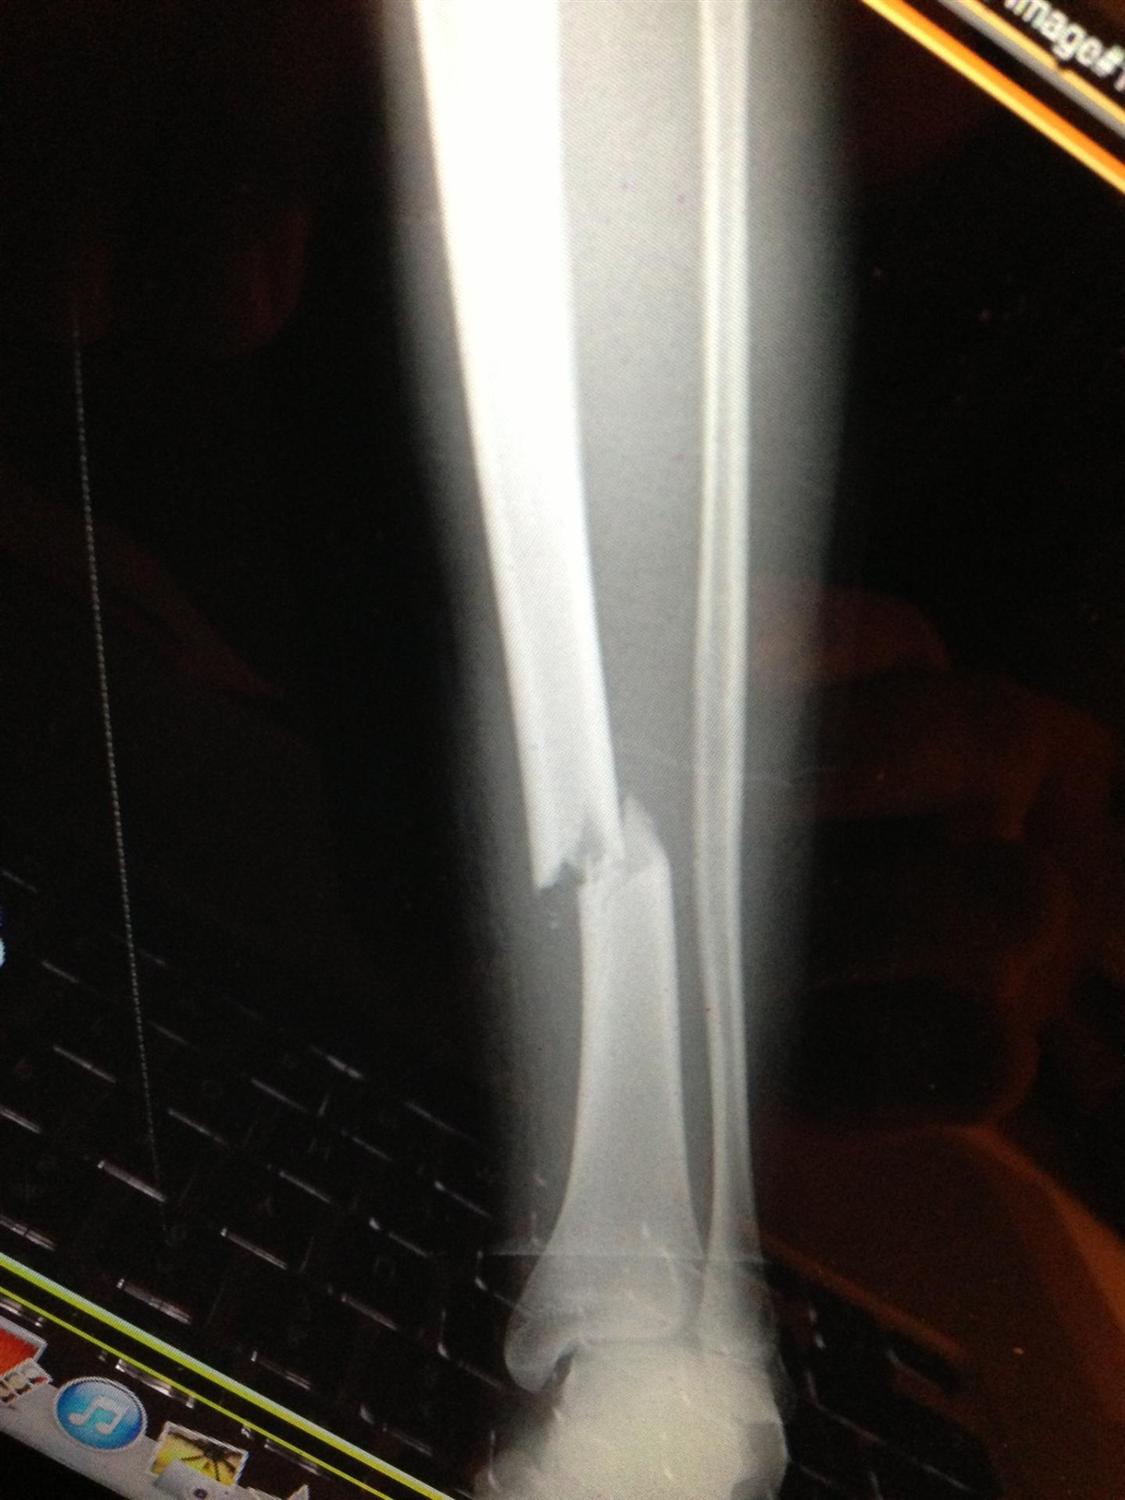

Tibia Shaft Fracture — Chicago Foot & Ankle Orthopaedic Surgeons

Return To Sport After Tibial Shaft Fracture . The main objectives of this scoping review were to summarise and make recommendations regarding firstly the return to running criteria. Intramedullary nail fixation remains the treatment of choice for unstable and displaced tibial shaft fractures in the adult. Rehabilitation goals • return to sport precautions • none unless otherwise indicated by md suggested therapeutic exercises • implement sport specific, multidirectional drills • begin. From the 16 studies with anterior tdsfs that resumed sports (n = 142),. Geier video, i discuss the process of getting an athlete with a tibia fracture back to sports. The goals of surgical treatment are to achieve osseous union. There are five important components to address prior to introducing running, which are: Time to return to sports anterior tibial stress fractures. A tibia fracture can be one of the most gruesome injuries in all of sports. While most adults need surgery, children and adolescents can often be treated in a cast.